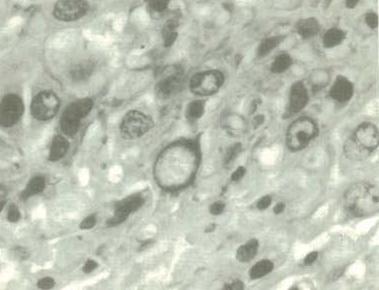

O resultado da dissecação - O derretimento do núcleo da célula tumoral e a desnaturação por concentração (foto 6); A Fragmentação do núcleo (foto 7); A morte natural de pequenos grupos (foto 8); Solidificação e necrose em uma extensa área de um grande grupo (foto 9); demonstrando claramente o efeito inibidor da multiplicação de células em cada tumor.

Foto 8: Núcleo em fragmentação

Foto 7: Núcleo em fragmentação

Foto 9: Solidificação e necrose de grande

grupo de células tumorais